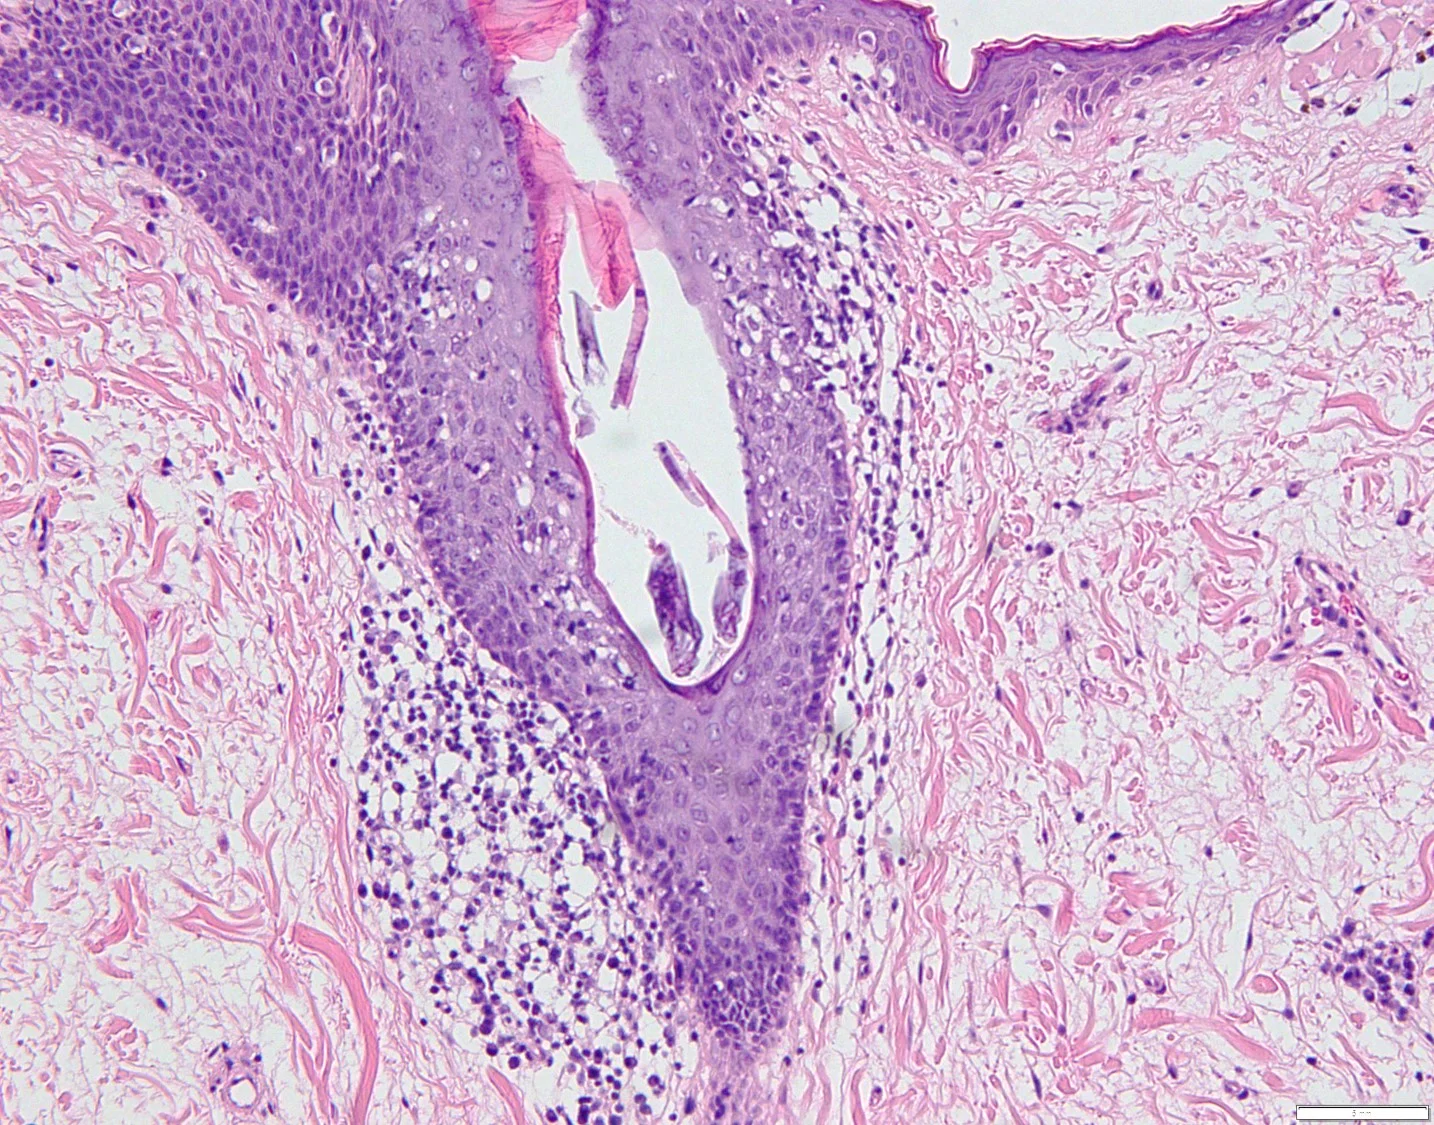

Histopathology: The sections showed a dense superficial and deep perivascular, perifollicular, and interstitial lymphoid infiltrate extending into the subcutaneous tissue. The lymphocytes were pleomorphic, intermediate to large, with irregular chromatin distribution and scattered mitoses. The overlying epidermis demonstrated subtle interface vacuolization with scattered single and collections of lymphocytes, suggestive of epidermotropism. There was no significant necrosis or vasculitis, but extravasation of erythrocytes with riming of fat by atypical lymphocytes was seen.

Immunohisochemical evaluation revealed tumor cells to be positive for CD2, CD3, CD56, TIA-1, and granzyme B, and negative for CD5, CD7, CD4, CD8, CD20, and CD123. Additionally, CD 30, Beta FI Gamma M1 were also negative. EBV-encoded RNA (EBER)-1 in situ hybridization was positive for EBV mRNA. RT-PCR T-Cell gene arrangement study was positive.

The histology and staining profile were consistent with EBV positive Extranodal NK/T-Cell Lymphoma.